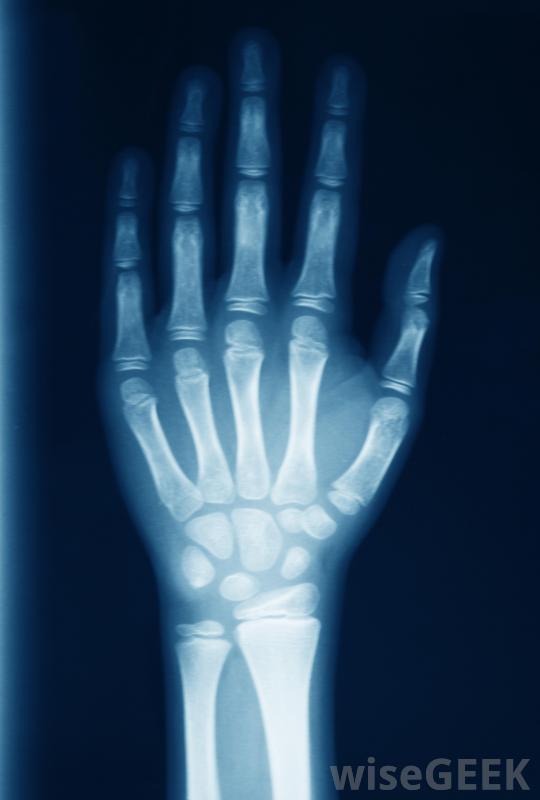

人类的手腕是一个非常独特的关节,因为它既是身体中最灵活也是最强壮的关节之一。它必须是灵活的,以允许手有广泛的运动范围,并且非常稳定,以允许手拿起和操纵重物。关节、骨骼、肌腱,而组成腕部的韧带则依靠软骨来缓冲,防止严重伤害。当手腕软骨因摔倒、扭伤、重复活动或关节炎而受损时,整个关节和手都会受到影响。如果不立即治疗,撕裂或减弱的软骨可能会导致长期不适甚至残疾。尽管x光可能不会显示早期关节炎损伤,它们可能显示疾病的进展。当人们的手腕因摔倒或突然扭伤而受到直接伤害时,腕关节软骨问题经常出现。当对手腕施加过大的压力和压力时,当一个人在摔倒时试图抓住自己时,手腕关节周围的软骨可能会拉伸和撕裂,其结果通常是炎症、肿胀、剧烈的局部疼痛和手部运动受限当人们因摔倒或突然扭伤手腕而受伤时,经常会出现腕关节软骨问题一个特别使人衰弱的问题是三角纤维软骨(TFC)撕裂,这是一个盘状的软骨区,用来缓冲尺骨、桡骨和腕关节中的一些较小的骨头和韧带。如果TFC和周围的韧带因受伤而撕裂,个体可能会遭受慢性疼痛,即使手不动,也会受到限制,肿胀和刺激会向下延伸到手指和手臂上,当试图弯曲手腕时,可能会听到咔嗒声。关节炎可能会导致软骨显著丧失反复过度使用关节也会导致腕关节软骨的问题。例如,一个需要挥动锤子的人,可能会在腕关节受到刺激和发炎。过度使用通常不会导致软骨组织撕裂,但软骨会变薄,导致移动手时可听到咔嗒声,手和握力无力,局部肿胀。手腕外伤可能使桡动脉搏动难以定位骨关节炎或类风湿性关节炎可导致手腕和身体其他关节的软骨组织分解腕关节炎会导致关节软骨严重丧失和过度劳损。许多患有骨关节炎或类风湿性关节炎的人都会感到关节疼痛、僵硬、肿胀和虚弱。如果不进行治疗,关节炎会导致腕关节变形和功能失调如果腕关节TFC和韧带撕裂,个体可能会经历慢性疼痛。腕关节软骨问题的治疗取决于病因。医生可以通过拍X光片或X光片和进行身体检查来检查手腕。关节炎的形式通常可以通过服用处方消炎药和止痛药来治疗,但晚期患者可能需要手术。手腕劳损可能在两到四周内通过充分休息和敷冰自行痊愈软骨撕裂通常需要手术和数周的康复治疗才能彻底愈合。骨关节炎是一种退行性疾病,其特征是关节软骨磨损类风湿性关节炎可导致手腕和其他关节的软骨组织分解受伤后在手腕上敷冰袋有助于减轻肿胀。